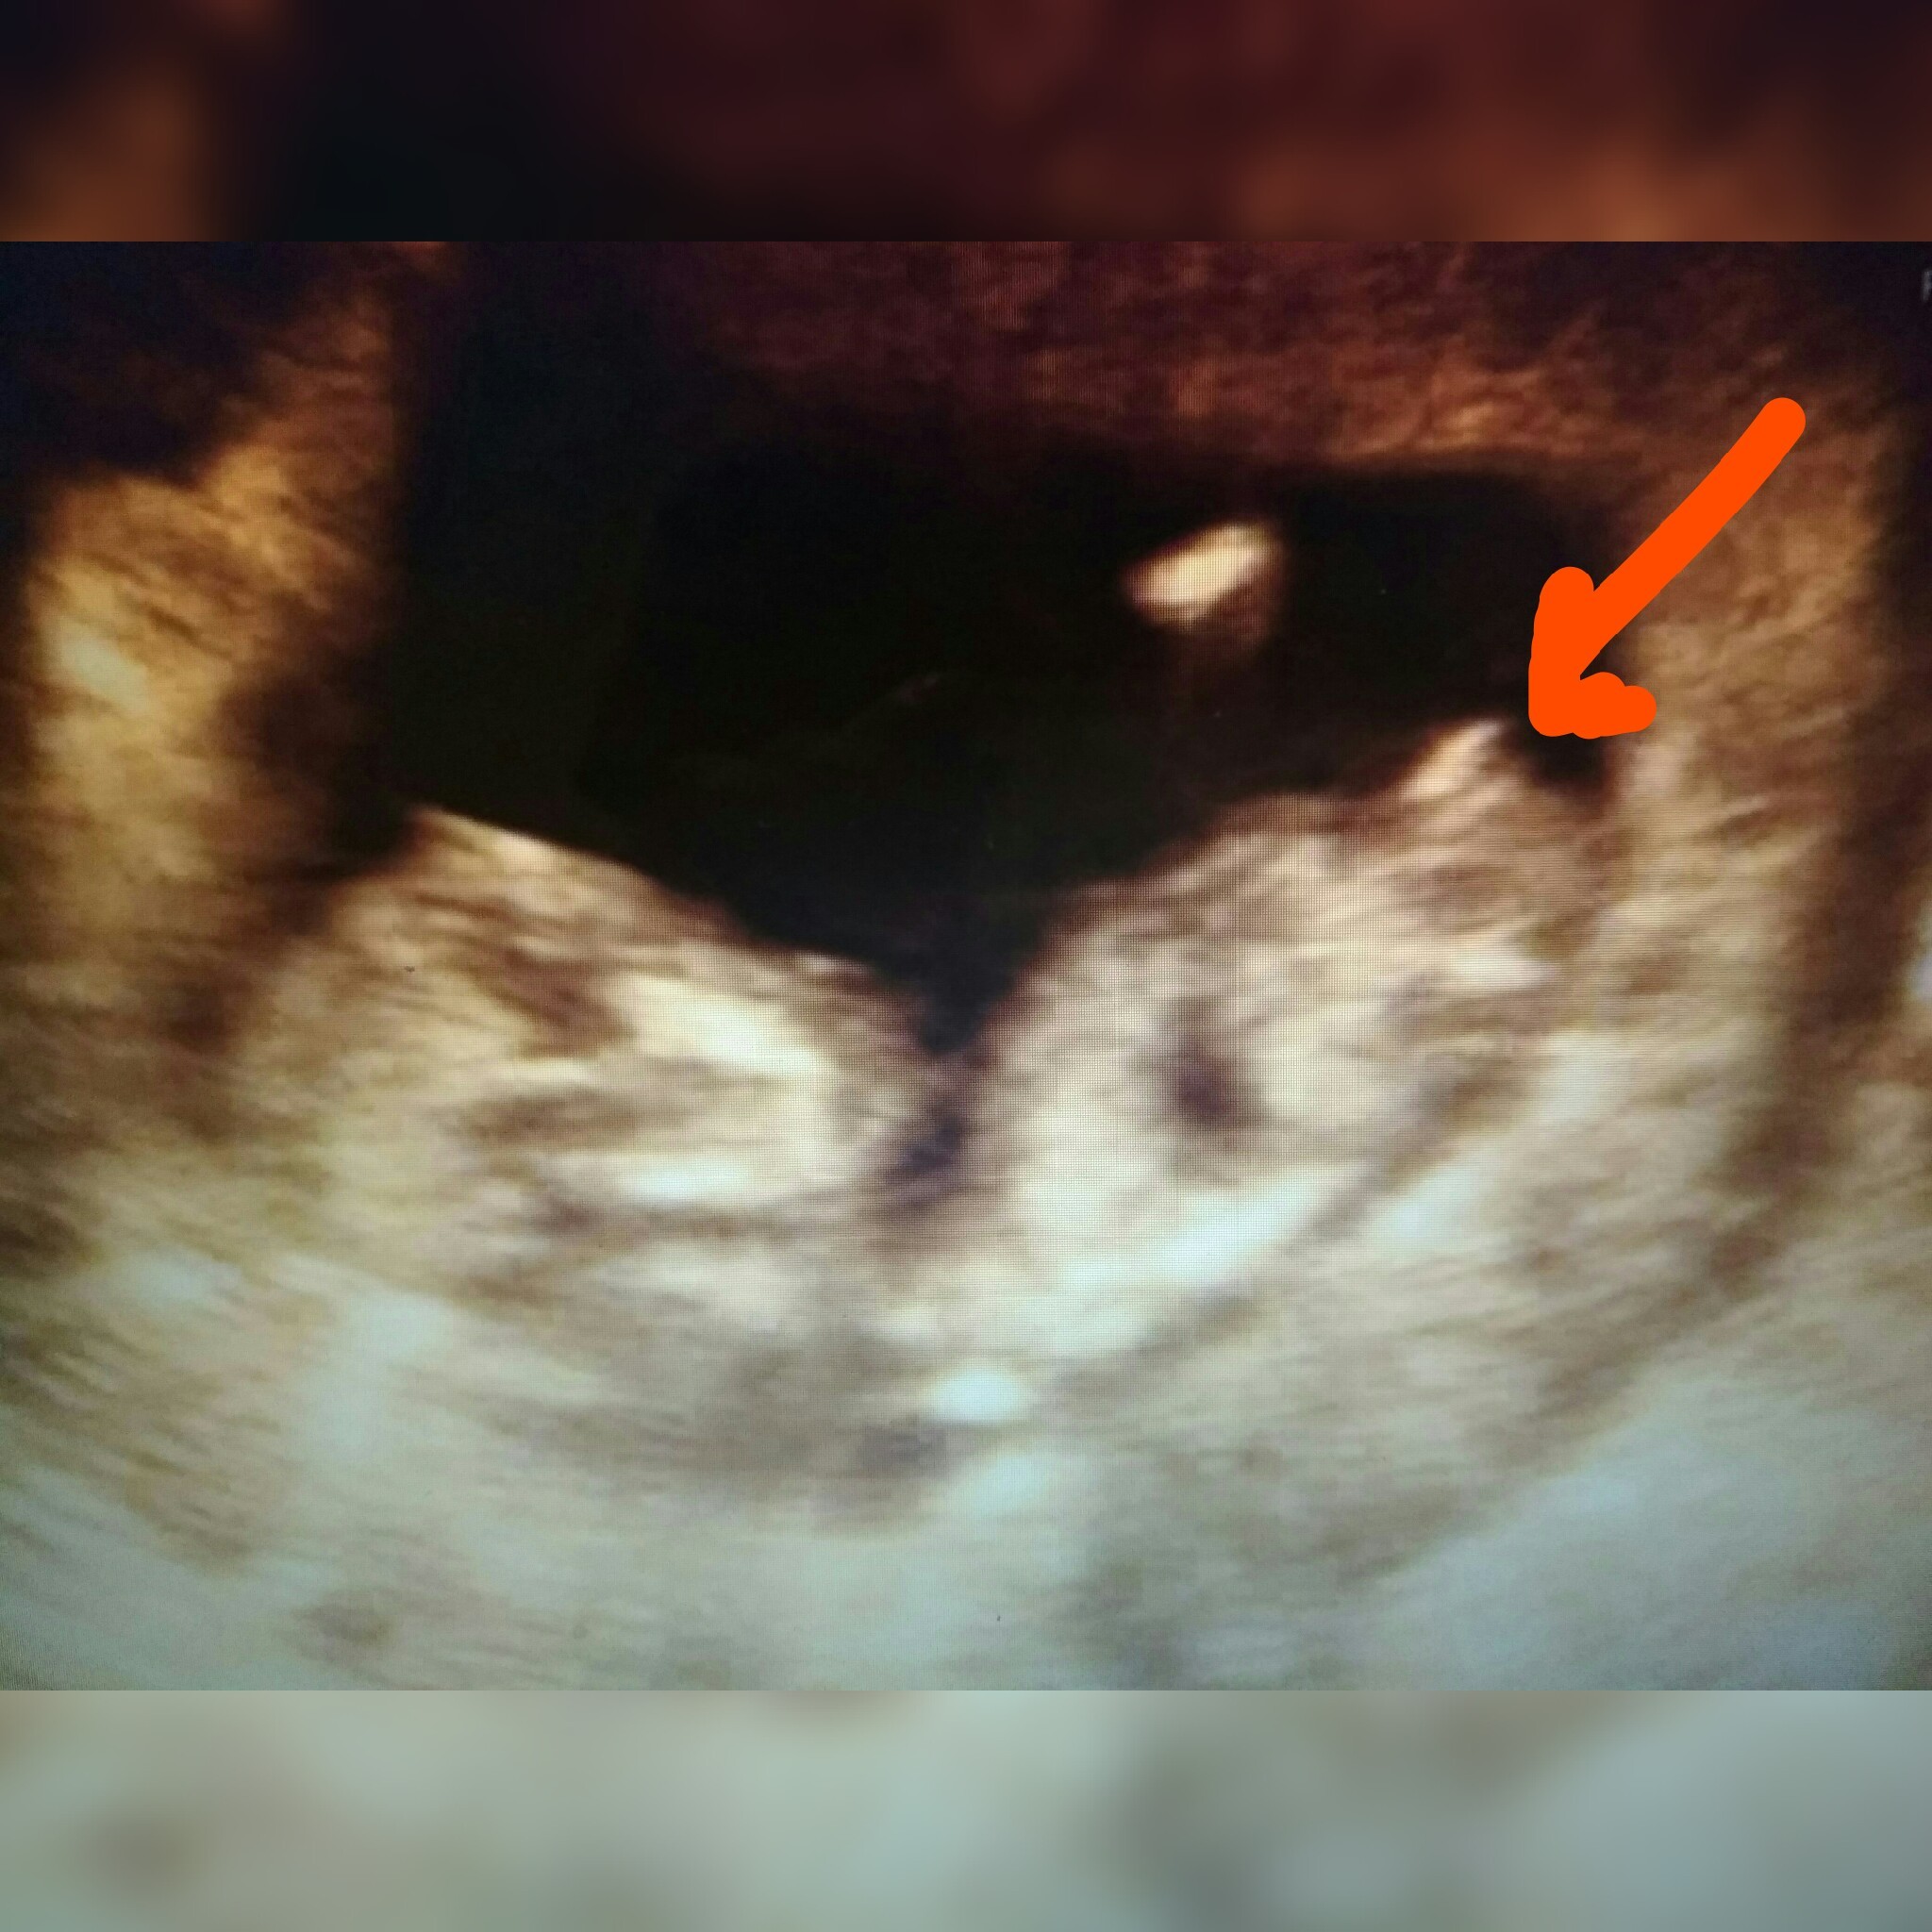

Jak myślicie widać już coś waszym zdaniem lekarz mówił,że prawdopodobnie chłopiec a ja wogle nic nie widzę...

Załączniki

• 1517991343798-540x870-270x435.png

1517991343798-540x870-270x435.png

39,7 KB · Wyświetleń: 1 158